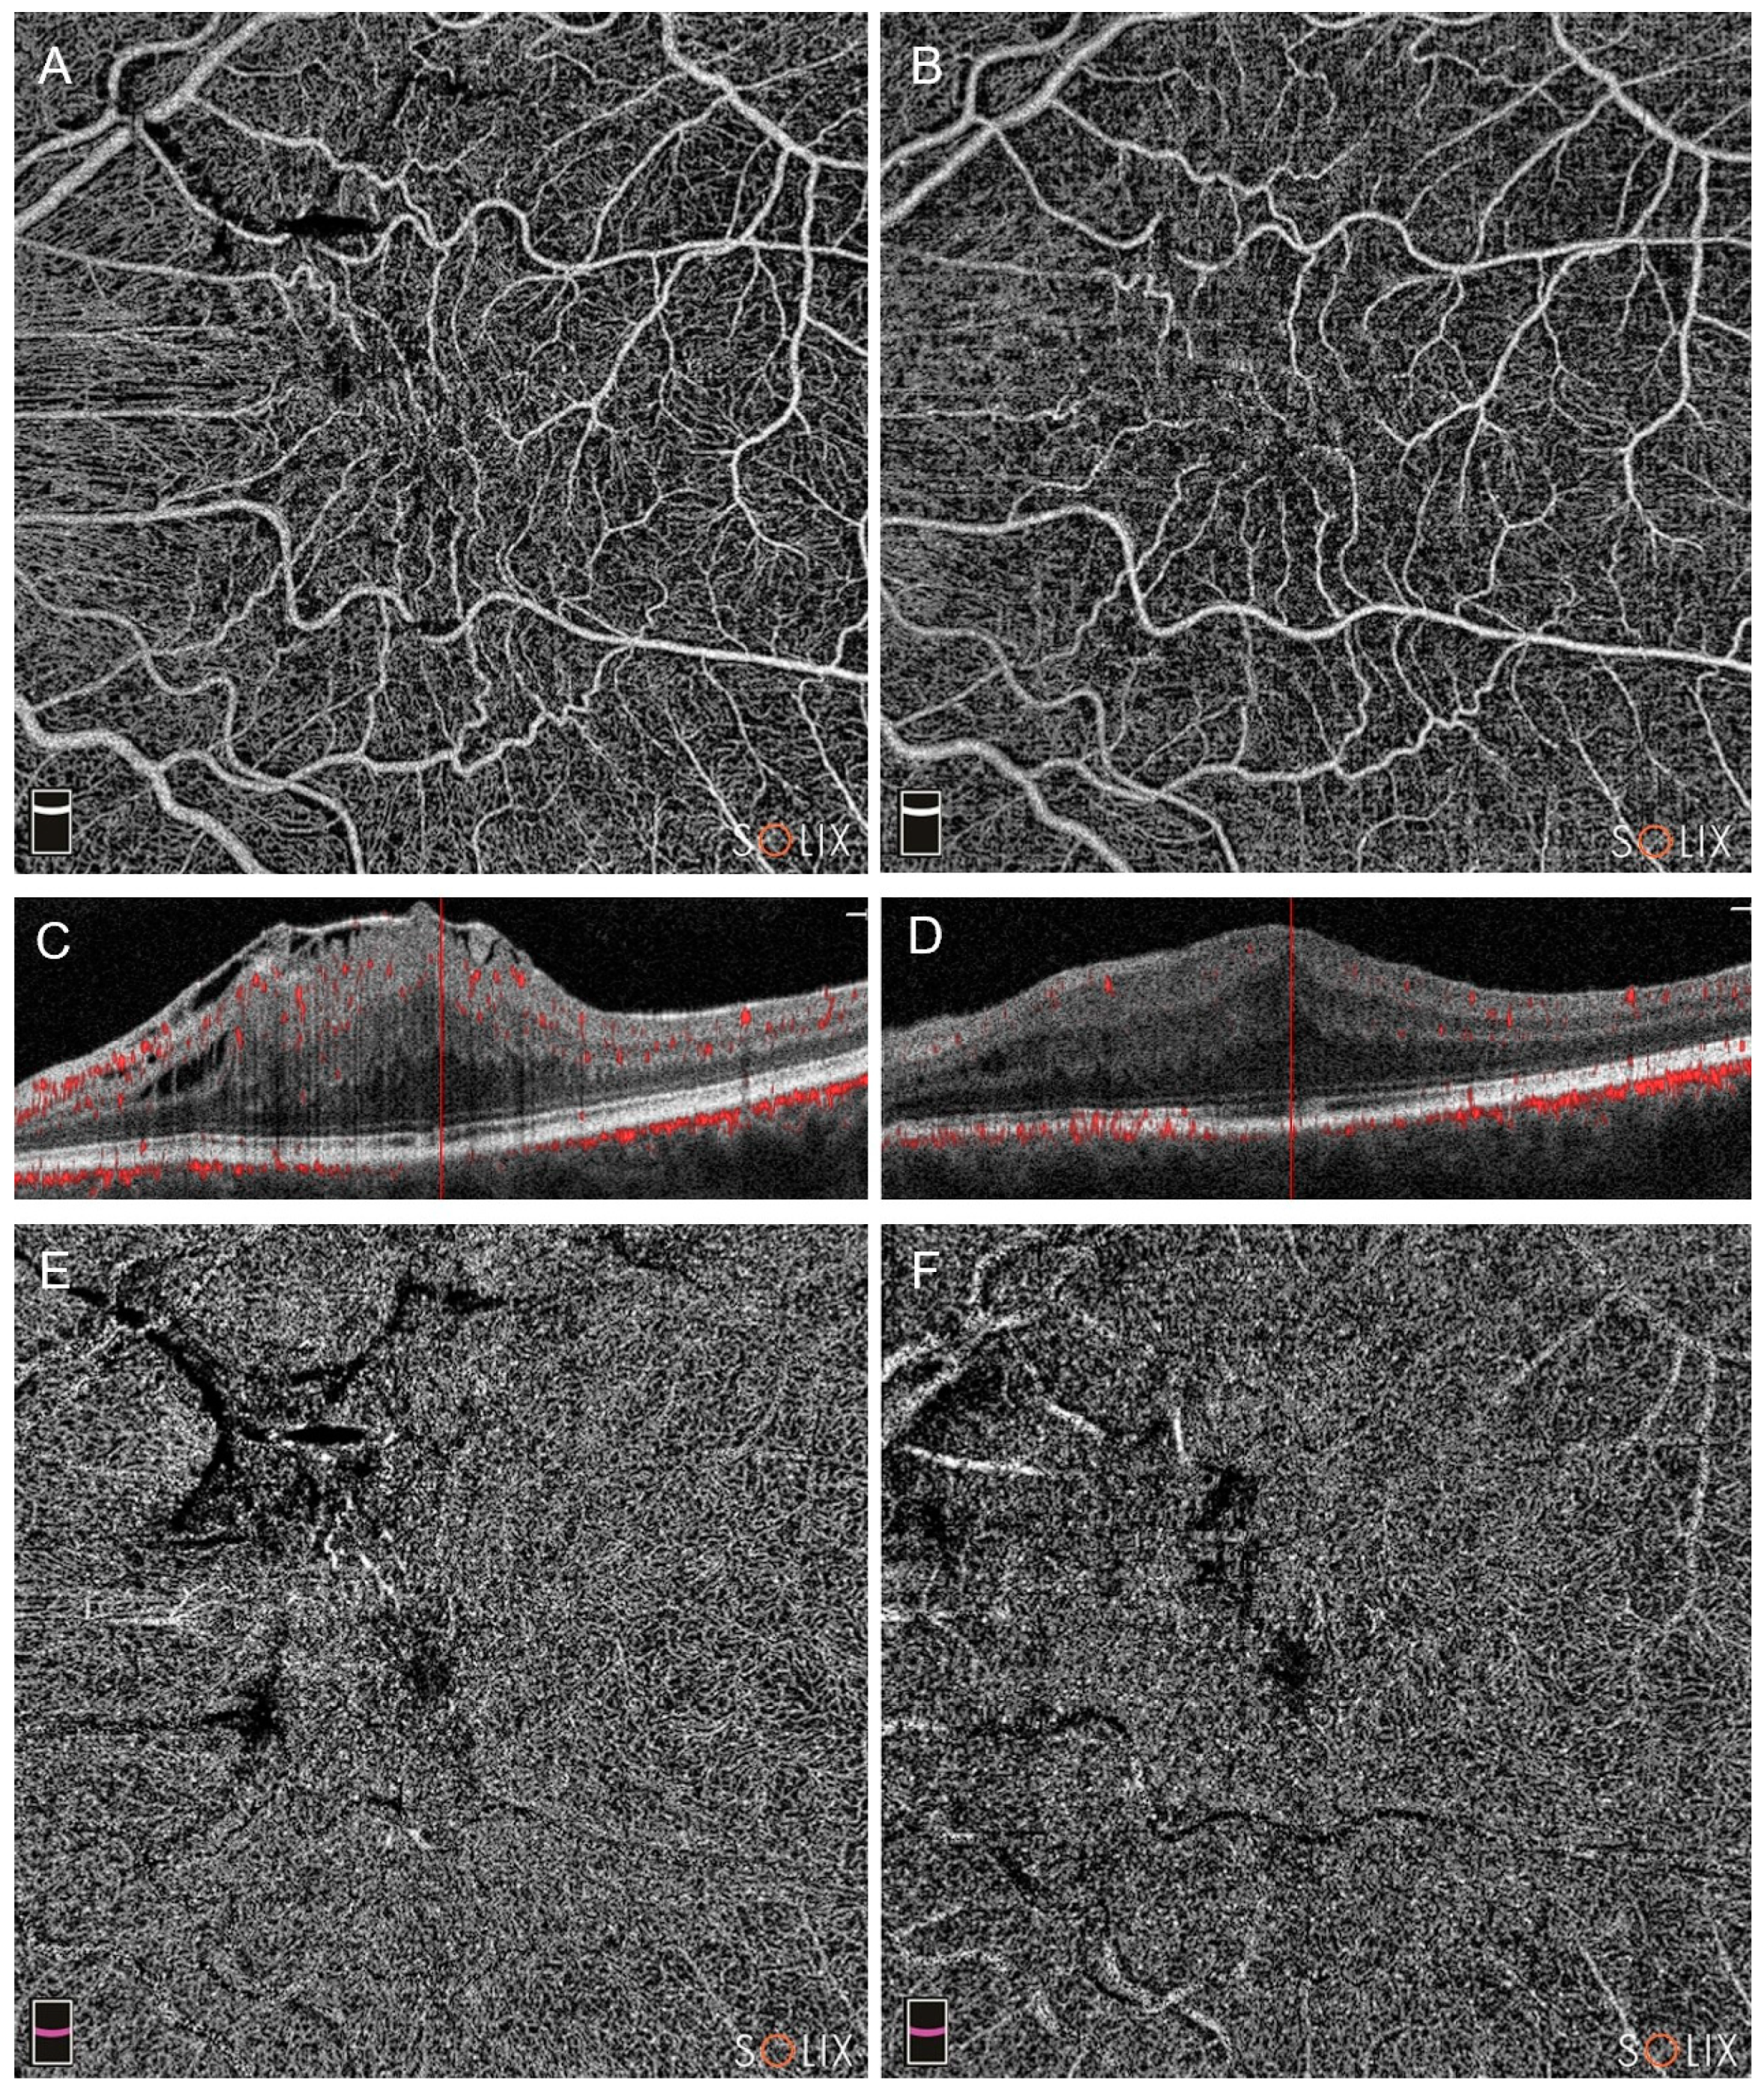

3.1. OCTA Findings